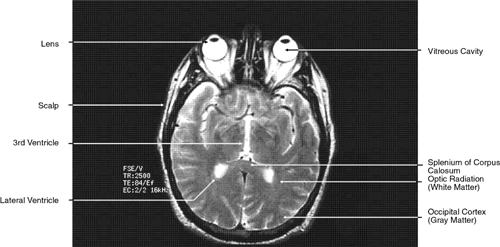

During MRI, the T1 and T2 differences between various tissues can be weighted to enhance the MR image produced. Essentially, this process increases the contrast between adjacent tissue structures and improves their visualization. This is ac-complished by varying within a particular pulse sequence either the repetition time (TR) betweenapplied radiofrequency pulses and the echo time(TE), or the time between the applied pulse andthe detection of the produced signal. A short TRfavors tissues with a short T1, such as fat. For exam-ple, with a TR of 300 msec, tissues will be enhanced in the following order: fat > white matter > gray matter > uvea > aqueous > vitreous, optic nerve, muscle > cortical bone. The reason for the intense response of fat is that with a short T1 it can almost completely recover its resting state between pulses. This enables it to respond again to the next pulse. Generally, T1-weighted images have a pulse sequence with a TR of 200 to 1,000 msec as well as a short TE (20 to 25 msec) (Fig. 7). The longer a particular tissue's T1, the less it can respond to the next pulse, because fewer of its protons have returned to a resting state. Therefore, its MR image is less intense. Lengthening the TR will allow more protons time to relax until the signal produced no longer depends on a tissue's T1. The image produced when the TR is long (2,000 to 2,500 msec) is “proton density”-weighted (Fig. 8). When this is the case, tissues with the highest proton density (e.g., gray matter and old hemorrhage) produce the most intense signal. In both T1- and proton density-weighted images, the TE is short (20 to 25 msec). The clearest anatomical delineation between tissues is provided by highly T1-weighted images with TR values between 300 and 500 msec.25,26

Fig. 7. Axial T1-weighted magnetic resonance imaging through midglobe.

Fig. 8. Axial proton-density magnetic resonance imaging through midglobe.

T2-weighted images can be produced at the same time as proton density images. In this case both the TR and TE are prolonged. By allowing all tissues to relax maximally, the most intense signal will be produced by the tissue with the longest T2 (that is, the tissue that remains coherent the longest). A particular tissue's T2, which typically ranges between 25 and 150 msec, is usually much shorter than its T1. To obtain a T2-weighted image, both the TR (>2,000 msec) and the TE (50 to 150 msec) are long (Fig. 9). In such cases, vitreous and cerebrospinal fluid give the most intense images and fat, white and gray matter, bone, and air give the least intense images.

Fig. 9. Axial T1-weighted magnetic resonance imaging through midglobe.

The globe is shown in Figure 12. The orbit and periorbital structures are shown in Figures 13 through 16, and the optic canal is shown in Figures 17 through 26. The cavernous sinus and optic chiasm are shown in Figures 27 and 28, and the posterior visual pathway and cranial nerves are shown in Figures 29 through 33.

GLOBE

Both MRI and CT are limited in their ability to image clearly the normal intraocular structures (see Fig. 12). For the most part this is due to the small size and ultrastructural composition of these structures. The cornea and sclera cannot be differentiated from each other but are quite distinct on both MRI and CT owing to their contrast with both the vitreous and aqueous internally and the orbital fat and, if present, air trapped behind the eyelids externally. The only other readily visible intraocular structure is the lens. On CT this appears uniformly dense and similar in appearance to the sclera. However, on T1-weighted MRI, the external lens capsule can be clearly differentiated from the internal lens structure owing to the presence of a significant number of hydrogen proteins within the central portion of the lens. In addition, the normal choroid, ciliary body, and iris can occasionally be visualized on MRI but not on CT. The normal retina cannot be seen by either technique; neither can the conjunctive, Tenon's capsule, angle structures, or the vessels and nerves penetrating the globe.